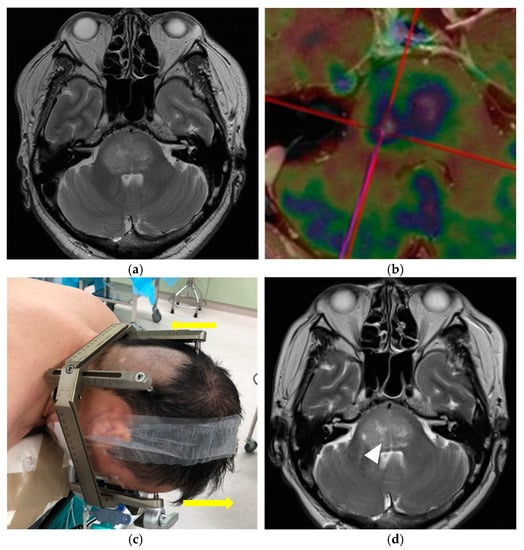

Before surgery, contrast-enhanced computed tomography (CT) and MRI were routinely performed, and nuclear medical examinations were performed via 18F-fluorodeoxyglucose positron emission tomography (18F-FDG PET) and single-photon emission computed tomography (SPECT), as needed to improve the accuracy of diagnosis (Figure 1a,b). Patients were fixed with a Leksell Coordinate Frame (Elekta AB, Stockholm, Sweden) under local anesthesia. The frame was fixed at four points on the forehead and the occiput. There were two important contrivances in the head fixation to facilitate the procedures. First, to fully expose the suboccipital area in which the burr hole would be placed, the posterior bar needed to be placed as low as possible while the occipital pins were placed above the superior nuchal line. Second, to leave the airway open for the anesthesia management, the frontal bar was placed slightly above the tip of the nose (Figure 1c). The head fixation was performed in the same fashion both for the adult and pediatric patients, but with caution, especially in the pediatric patient, due to the variability in the thickness of the developing skull. Subsequently, stereotactic, contrast-enhanced, thin-slice CT or contrasted time-of-flight MRI with a slice thickness of 1 mm was performed to safely and accurately define the surgical trajectory for collection of the tumor specimen. For patients with less-contrast-enhanced tumors, the tumor target was defined with a combination of thin-slice fluid-attenuated inversion recovery (FLAIR), T2-weighted MRI, PET, and/or SPECT images. As per our policy, the stereotactic CT is performed for pediatric cases under 12 years old instead of MRI to shorten the examination time with the fixation, considering the risk of body movement during the imaging examination. In principle, the target is set at the site of a well-enhanced lesion that extends to the cerebellar peduncle. When the tumor has spread extensively, the highly active component can be determined by PET and/or SPECT. During preoperative planning, we used the infratentorial transcerebellar approach with the patient in the prone position for all cases. The surgical trajectories were set through the cerebellar peduncle to the brainstem tumor, aiming for postoperative neurological preservation by using the FrameLink software (Elekta AB) (Figure 1d). Specifically, we avoided the nerve nuclei and tracts and confirmed that there were no arteries, veins, or cerebellar sulci along the trajectory.

Figure 1.

A 60-year-old man presented with headache, diplopia, and ataxia (Case 18). (a,b) Magnetic resonance imaging (MRI) and positron emission tomography (PET) revealed a pontine tumor extending also to the right thalamus, bilateral medial temporal lobe, right mesencephalic tegmentum, medulla oblongata, and bilateral cerebellum (maximum diameter: 37 mm, tumor volume: 17.8 mL); the surgical trajectories are set through the right middle cerebellar peduncle to the brainstem tumor, aiming for postoperative neurological preservation by using the FrameLink software installed in StealthStation S7 surgical navigation system (Medtronic plc); (c) Surgical setup for stereotactic frame-based biopsy (SFB) of a brainstem tumor. The physical characteristics of this patient are a large head size, short neck, and well-developed occipital muscles. The frame was fixed at four points on the forehead and back of the head by shifting the frontal pins slightly upward from the orbitomeatal baseline (arrow), to reduce the possibility of interference with the surgical field, which comprised a skin incision and burr hole; (d) No hemorrhage was observed on the MRI performed within 24 h after surgery. The tumor specimen was obtained from the targeted location (right middle cerebellar peduncle; arrowhead); (e) Histologic features of a diffuse midline glioma. Hematoxylin and eosin staining showing the diffuse growth of atypical glia cells with round nuclei; (f) Immunohistologic staining showing that the atypical cells are positive for H3K27M.